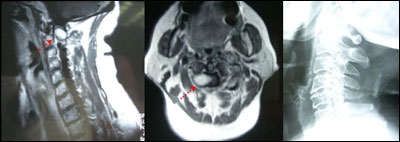

女性,65岁,双手麻木2月,右侧明显。查体:右侧C2-3分布区针刺痛觉减退,余无异常。

术前图片: